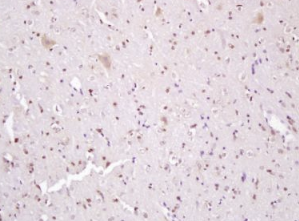

组织/细胞:大鼠脑组织;4%多聚甲醛固定石蜡包埋;

抗原提取:柠檬酸缓冲液(0.01M,pH 6),15min煮沸,用3%过氧化氢阻断内源性过氧化物酶30min;37℃下阻断缓冲液(正常山羊血清)20 min;

孵育:抗磷酸β-连环蛋白(Tyr142)多克隆抗体,未结合1:200,在4°C下过夜,然后接合到二级抗体和DAB染色。